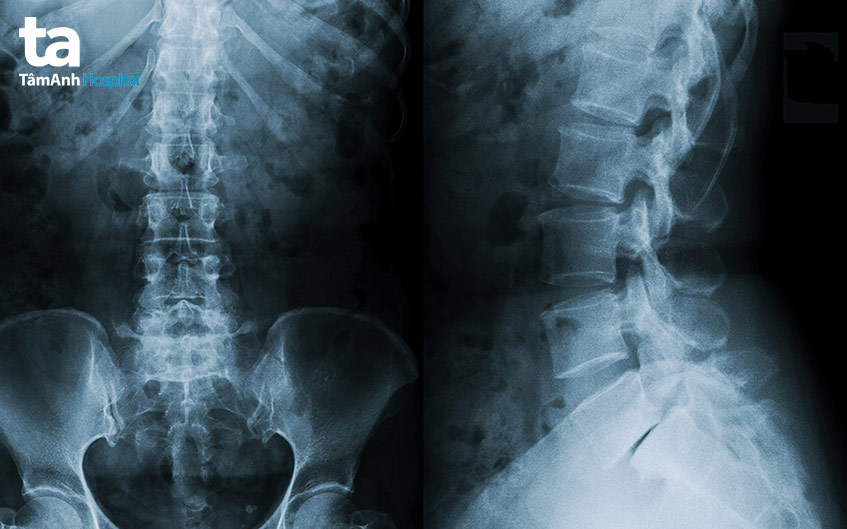

Đây là một trong những nguyên nhân hàng đầu dẫn đến chứng đau mỏi vai gáy tê chân tay. Cụ thể, cột sống có chứa hệ thống các dây thần kinh quan trọng. Khi có bất kỳ tổn thương nào xảy ra, những dây thần kinh này đều có nguy cơ bị chèn ép, từ đó biểu hiện ra ngoài với triệu chứng nhức mỏi, đau, tê bì… Một số bệnh lý điển hình thường gặp gồm:

Đây là tình trạng thoái hóa bất thường xảy ra giữa các đốt sống của cột sống và đĩa đệm. Thoái hóa đốt sống thường gây ra hiện tượng đau mỏi cổ vai gáy mãn tính.

Tình trạng này xảy ra khi một trong các đĩa đệm giữa 26 đốt sống của cột sống bị vỡ. Lúc này, (dịch bên trong bị rò rỉ, gây ảnh hưởng đến tủy sống) nhân nhầy đĩa đệm thoát ra khỏi vị trí ban đầu, xuyên qua các dây chằng vào ống sống, gây chèn ép các thành phần trong ống sống bao gồm tủy sống hoặc dây thần kinh gần đó, dẫn đến đau mỏi vai gáy, đau lưng, thậm chí là tê bì chân tay. Cơn đau do thoát vị đĩa đệm cổ thường có xu hướng chuyển biến nghiêm trọng hơn khi nâng vật nặng, vận động hoặc vặn mình.

(Đây là tình trạng canxi lắng đọng và bám vào thân đốt sống, dẫn đến hình thành các gai xương) Gai cột sống là phần xương nhỏ phát triển phía rìa xương đốt sống. Khi xương và các thành phần quanh xương bị tổn thương hoặc kích thích, cơ thể phản ứng bằng cách cố gắng sửa chữa vùng tổn thương, cuối cùng hình thành gai xương. Gai xương có thể gây ra triệu chứng hoặc không, phụ thuộc vào vị trí, mức độ phát triển. Khi rễ thần kinh ống sống bị chèn ép bởi gai cột sống sẽ khiến vùng cổ vai gáy bị đau, khó vận động.

Ngoài ra, một số vấn đề bất thường khác liên quan đến cột sống như hẹp ống sống, viêm cột sống dính khớp… cũng đem đến những ảnh hưởng tương tự. Theo đó, những triệu chứng dễ nhận biết nhất gồm: